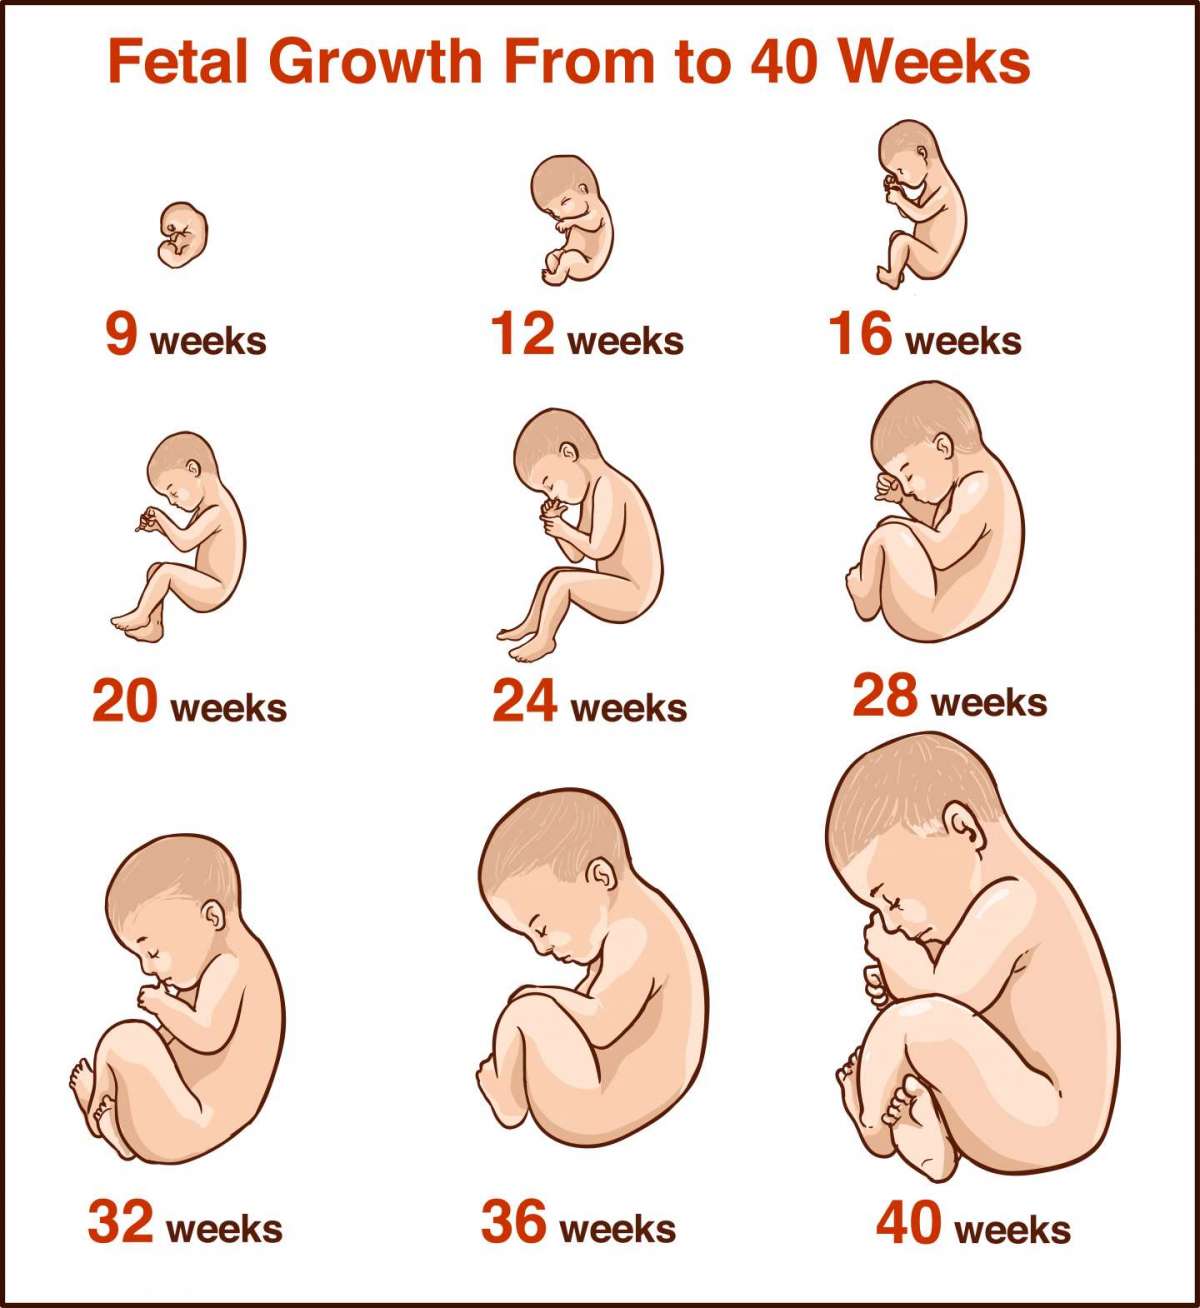

Lo Sviluppo dell Embrione Feto

Come calcolare la lunghezza del feto Pourfemme

Misure del feto di settimana in settimana Pazienti

Product code: Misura piede feto onlinePeso e lunghezze del feto online, Tabelle crescita fetale CRL BPD CC CM CA FL feto online, Tabelle crescita fetale CRL BPD CC CM CA FL feto online, Tabelle fetali online, Tabelle fetali online, Tabelle crescita fetale CRL BPD CC CM CA FL feto online, Tabella crescita feto. Percentili peso e lunghezza feto online, Tabelle fetali online, Tabelle crescita fetale CRL BPD CC CM CA FL feto online, Tabelle crescita fetale CRL BPD CC CM CA FL feto online, Tabelle fetali online, Tabelle crescita fetale CRL BPD CC CM CA FL feto online, Tabella crescita feto. Percentili peso e lunghezza feto online, Tabelle di crescita del feto settimana per settimana online, Ecografia fetale morfologica o strutturale del II trimestre online, Tabelle di crescita del feto settimana per settimana online, CROMOSOMOPATIE online, Trentesima Settimana Di Gravidanza Settimana 30 online, Tabelle crescita fetale CRL BPD CC CM CA FL feto online, Tabelle di crescita del feto settimana per settimana online, Le misure del feto come calcolarle online, La gravidanza mese per mese sviluppo fetale e cambiamenti nella madre online, Trentottesima Settimana Di Gravidanza Settimana 38 online, Pedimetro online Calcola la taglia del piede del tuo bambino La online, Ecografia Morfologica Dr Annona online, 16 settimana di gravidanza ecografia lunghezza e peso del feto online, 19 settimana di gravidanza dove si trova il bambino HiPP Biologico online, Lo sviluppo del feto tra la 33 e la 40 settimana Nostrofiglio online, Tabella crescita feto. Percentili peso e lunghezza feto online, Lo Sviluppo dell Embrione Feto online, Sproporzione cefalo pelvica Danni Da Parto Legal online, La pratica dell ostetricia concepita per l uso di studenti e online, Lo Sviluppo dell Embrione Feto online, Reflessologia Libro 1 Il Piede tra Micro e Macrocosmo online, Come calcolare la lunghezza del feto Pourfemme online, Misure del feto di settimana in settimana Pazienti online, Med 2000 eco online, Feto a 5 settimane immagini e fotografie stock ad alta risoluzione online, Tabella crescita feto. Percentili peso e lunghezza feto online, Sviluppo del feto online, CROMOSOMOPATIE online, Lunghezza piede bambino e numero scarpa Nostrofiglio online, In gravidanza crescono i piedi Focus online, Lunghezza del feto perch importante misurarla Uppa online, Ecografia Morfologica Centro Diagnosi Prenatale online, La crescita del feto settimane dalla 8 alla 12 online, ProMamma online, PIEDE TORTO ilpiedetorto online, Piedi in gravidanza attenzione all alluce valgo PBS online, Perdita di liquido amniotico e danni al neonato Danni Da Parto Legal online.